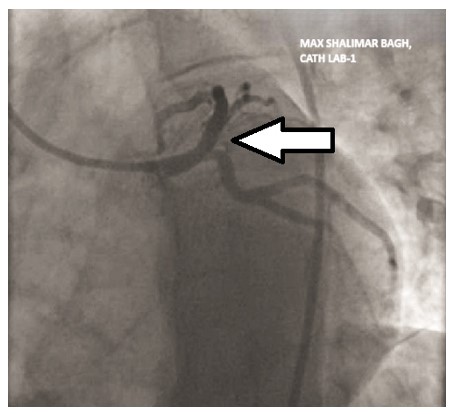

Wellens syndrome is a distinct electrocardiographic (ECG) finding that reflects critical narrowing of the proximal left anterior descending (LAD) coronary artery. First identified in 1982, this pattern typically appears in patients with a history of unstable angina, especially during pain-free intervals. Recognizing this syndrome is vital, as it signals a high risk for imminent anterior wall myocardial infarction if not treated promptly. The syndrome is classified into two types based on T wave morphology. Type A, which features biphasic T waves most prominently in leads V2 and V3, can be particularly challenging to identify. These subtle ECG changes are often overlooked, especially when the patient is not actively experiencing chest pain, which increases the risk of misdiagnosis or delayed treatment. Such oversight can lead to rapid deterioration and serious cardiac complications, including extensive myocardial infarction. In this case report, we present a patient with type A Wellens syndrome, where the early ECG showed only mild biphasic T wave abnormalities that were initially missed. This diagnostic oversight delayed appropriate cardiologic intervention and emphasized the importance of vigilance in evaluating atypical or transient ECG changes. Early identification of Wellens syndrome, even in asymptomatic phases, is critical to guiding appropriate management and preventing life-threatening outcomes. Clinicians, particularly in emergency medicine settings, should be aware of these subtle yet significant ECG markers.